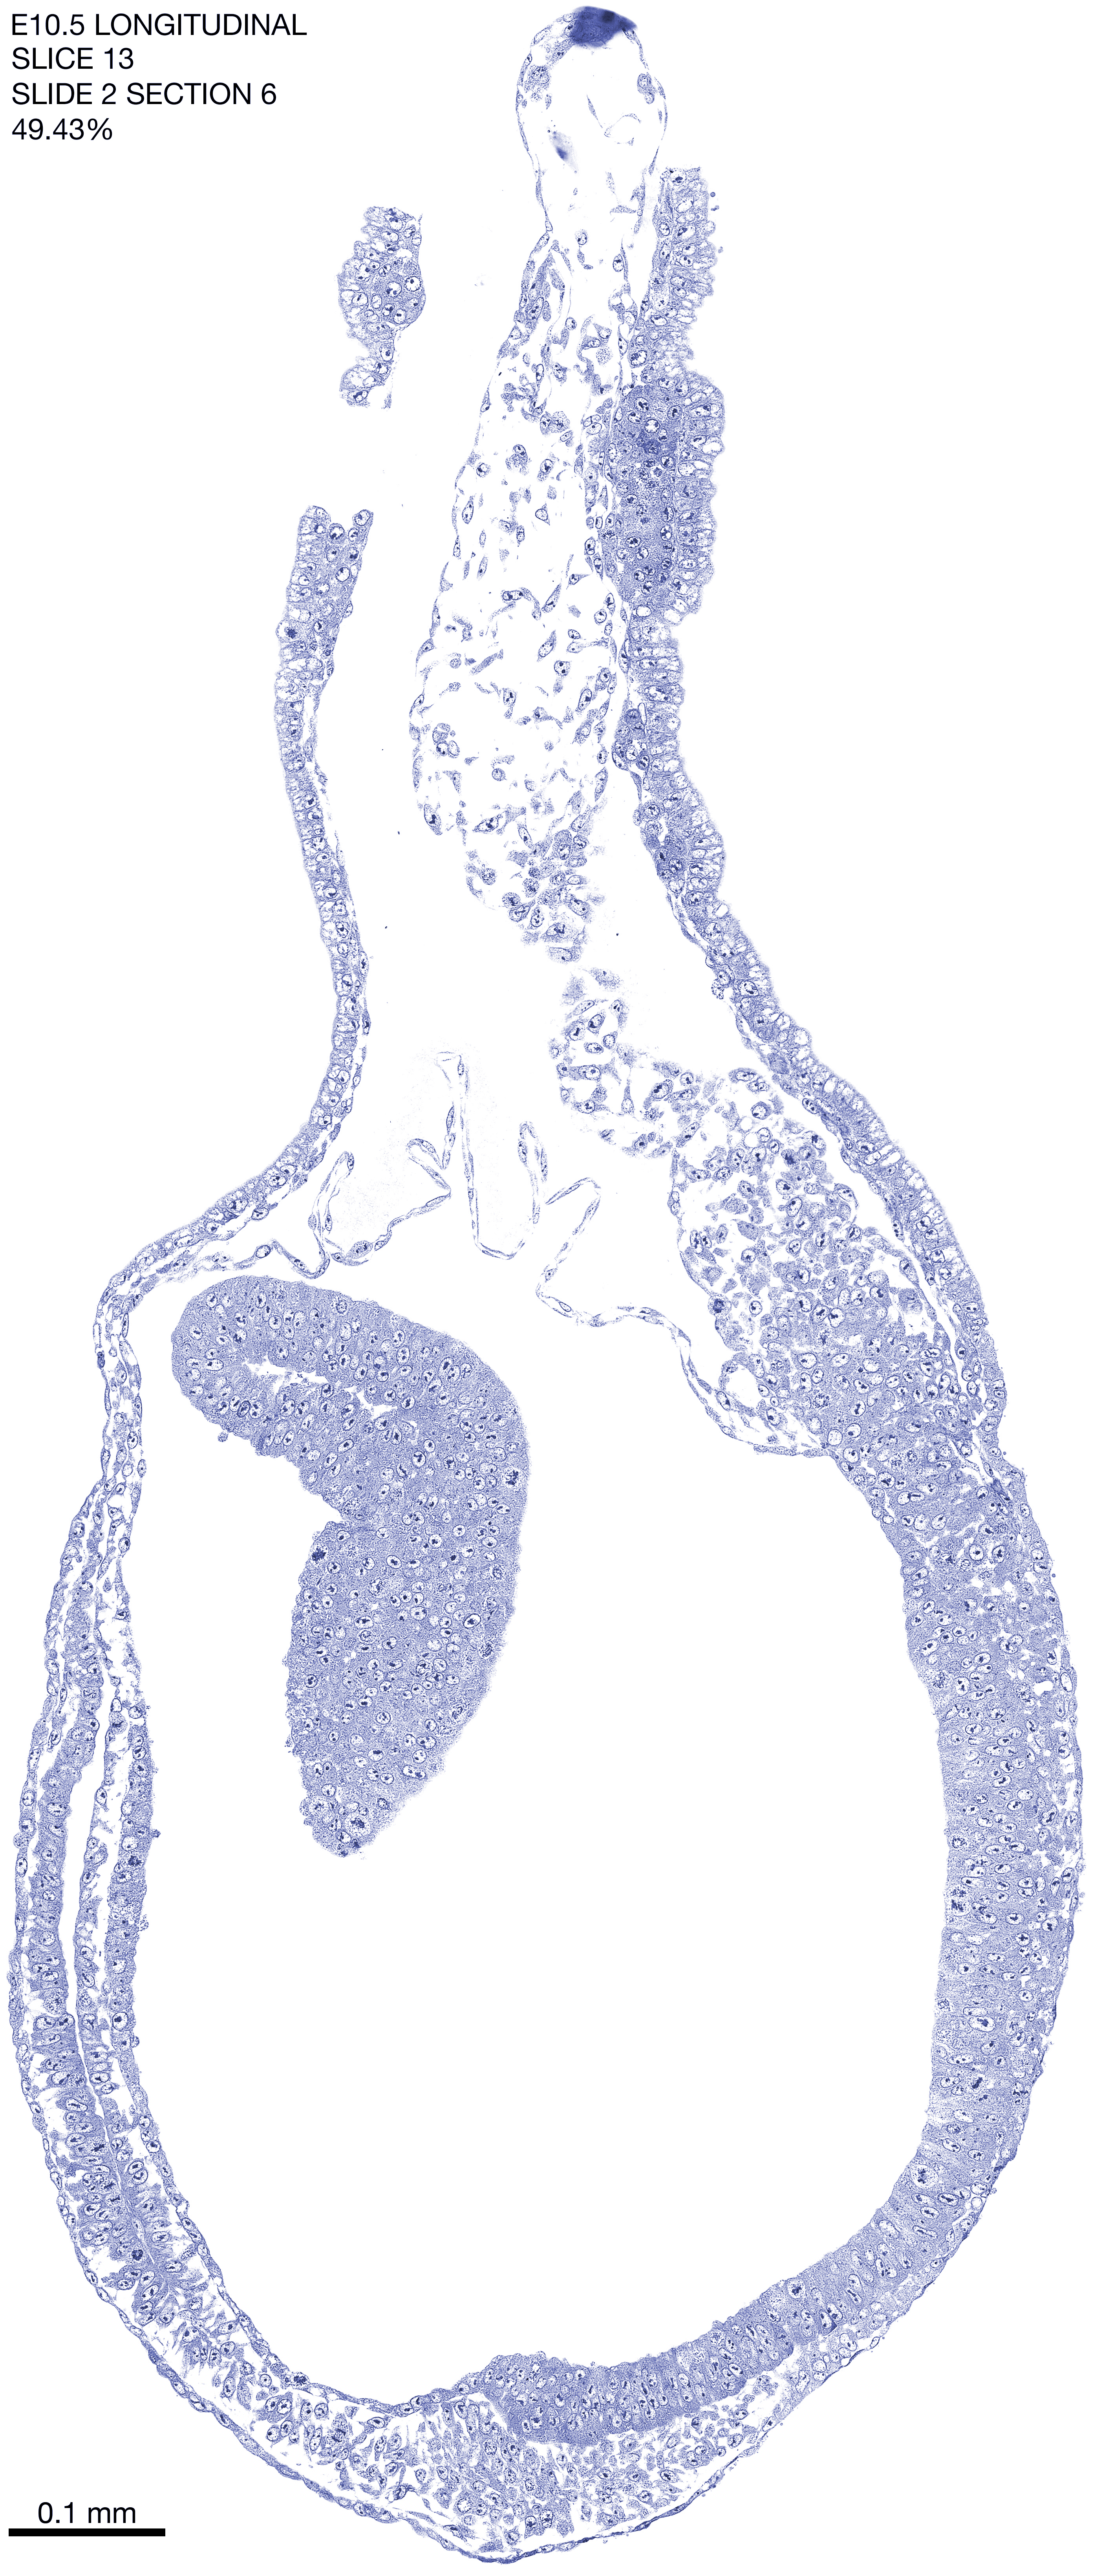

E10.5 Longitudianal Archive This page contains jpg files of ALL SLICES (each 3µm thick) that were scanned of the E10.5 longitudinally cut specimen. Download: Large | High Res Download: Large | High Res Download: Large | High Res Download: Large | High Res Download: Large | High Res Download: Large | High Res Download: Large | High Res Download: Large | High Res Download: Large | High Res Download: Large | High Res Download: Large | High Res Download: Large | High Res Download: Large | High Res Download: Large | High Res Download: Large | High Res Download: Large | High Res Download: Large | High Res Download: Large | High Res Download: Large | High Res Download: Large | High Res Download: Large | High Res Download: Large | High Res Download: Large | High Res Download: Large | High Res Download: Large | High Res Download: Large | High Res Download: Large | High Res Download: Large | High Res Download: Large | High Res Download: Large | High Res Download: Large | High Res Download: Large | High Res Download: Large | High Res Download: Large | High Res Download: Large | High Res Download: Large | High Res Download: Large | High Res Download: Large | High Res Download: Large | High Res Download: Large | High Res Download: Large | High Res Download: Large | High Res Download: Large | High Res Download: Large | High Res Download: Large | High Res Download: Large | High Res Download: Large | High Res Download: Large | High Res Download: Large | High Res Download: Large | High Res Download: Large | High Res Download: Large | High Res Download: Large | High Res Download: Large | High Res Download: Large | High Res Download: Large | High Res Download: Large | High Res Download: Large | High Res